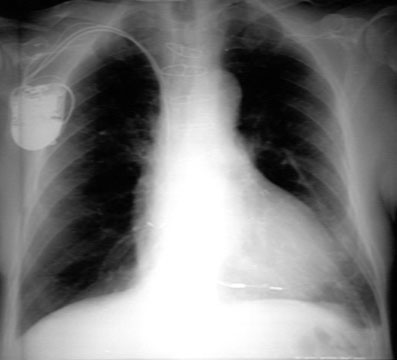

Note the large subcarinal mass in a patient with previously resected left lower lobe lung cancer.